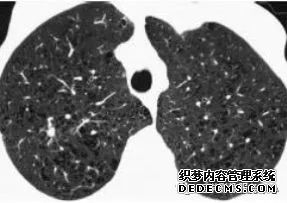

肺转移瘤的十种不典型CT表现